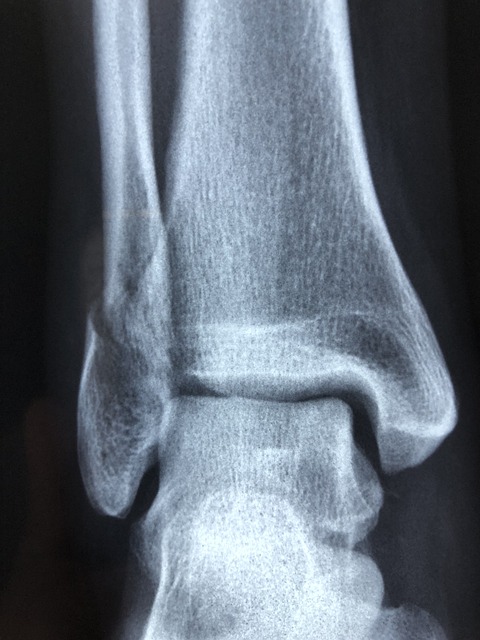

“Una malattia- prosegue l’esperto- che è in forte crescita nel mondo e anche in Italia, legata principalmente al fenomeno dell‘invecchiamento della popolazione. Sappiamo che il nostro è il Paese con il più alto numero di ultra 65enni, siamo al 20%, e abbiamo un numero altissimo di ultra ottuagenari: è proprio questa la fascia critica dello sviluppo di patologie importanti come l’osteoporosi, che anni fa, come Aila, definimmo ‘il tarlo silenzioso‘, proprio perchè questa malattia si manifesta solo nel momento in cui sono evidenti le complicanze, ovvero le fratture, del femore e della colonna vertebrale”.

Il coordinatore della Commissione per l’osteoporosi dell’Omceo Roma si sofferma su alcuni dati che accomunano entrambi i sessi. “L’osteoporosi- rende noto- interessa circa il 20% delle donne in età post menopausale, un fatto riconducibile alla mancanza degli ormoni estrogeni che hanno la funzione di bilanciare il ricambio del calcio nelle ossa. Ma la patologia colpisce anche gli uomini dopo i 65 anni e può interessare fino al 6% della popolazione”.

Fare prevenzione significa, dunque, prevenire le fratture. “Dieci anni fa- dichiara- l’Aifa parlava di centomila fratture vertebrali nel nostro Paese. Fratture che producono un danno economico per le spese primarie di circa 1 miliardo. E oltre al costo assistenziale si registra un disagio sociale: la persona, infatti, non cammina, non sta in piedi e i suoi familiari perdono spesso intere giornate di lavoro”.

Il coordinatore della Commissione per l’osteoporosi parla anche di diagnosi precoce. “Si fa con la Moc, strumento fondamentale in grado di verificare in maniera matematica il nostro patrimonio osseo. Si svolge una volta all’anno e consente di verificare se stiamo perdendo tale patrimonio. E se questo accade, significa che ci stiamo avvicinando al rischio di frattura”.